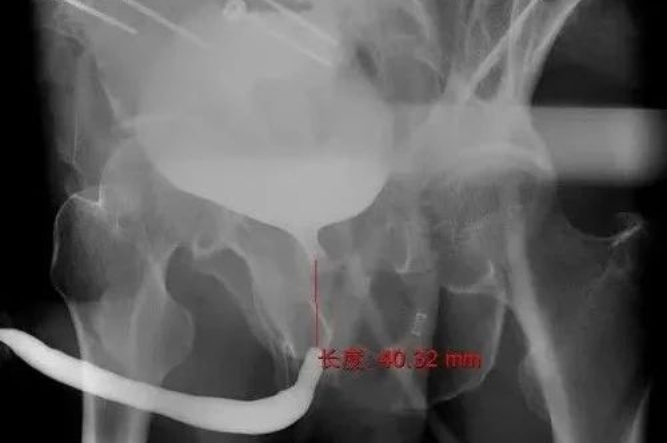

影像學(xué)結(jié)果顯示,尿道膜部連續(xù)性中斷,狹窄段長(zhǎng)達(dá)4cm。結(jié)合患者傷情及影像結(jié)果,為徹底拔除“膀胱造瘺”,恢復(fù)尿道連續(xù)性,重建生活質(zhì)量,泌尿外科團(tuán)隊(duì)決定為劉師傅實(shí)施經(jīng)會(huì)陰途徑后尿道修復(fù)重建手術(shù)。